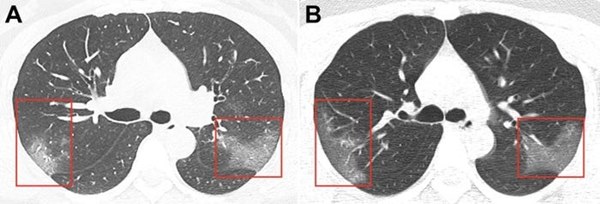

Hình chụp CT hai lá phổi của một bệnh nhân nữ 33 tuổi ở Lan Châu, Trung Quốc. Trong hình A, có nhiều "đốm trắng" mờ như thủy tinh ở thùy phải và sau đỉnh thùy trái. Hình B là phổi chụp sau 3 ngày theo dõi bệnh nhân. Nó cho thấy những đốm trắng ngày càng lan rộng bên trong phổi người bệnh, "xâm chiếm" đỉnh sau thùy phải và sau đỉnh của thùy trái. Ảnh: RSNA.